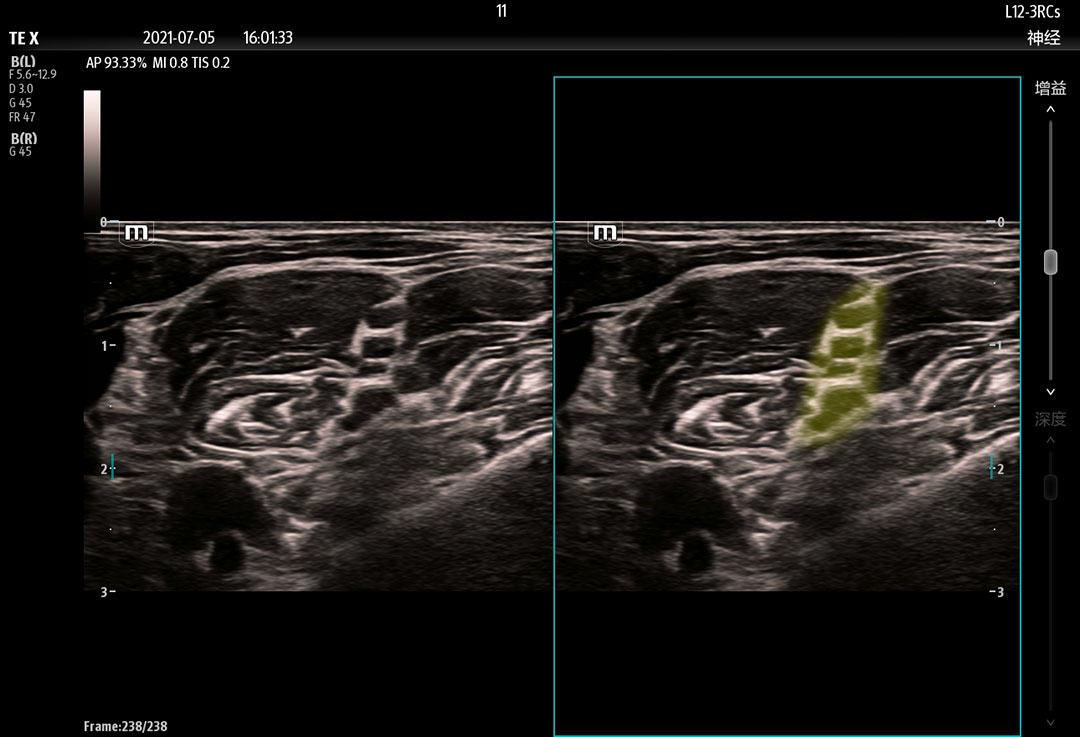

The technology-rich TE X Ultrasound System gives clinicians access to market-leading artificial intelligence (AI)-powered Smart Tools, an ergonomically designed system, and proprietary software-based beamformer Zone Sonography Technology+ (ZST+). By incorporating these elements, the TE X Ultrasound System provides access to advanced diagnostic data, the ability to adapt to the various clinical scenarios at point of care, and best-in-class imaging to help them provide a higher standard of care.

Needle Guidance